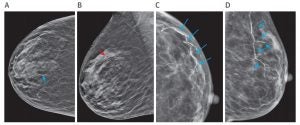

En ese contexto, recientemente se ha propuesto que la detección de calcificación en las arterias mamarias puede ayudar a mejorar la detección y evaluación del riesgo de ECV en mujeres aparentemente sanas.

Esta revisión proporciona una visión general de la anatomía arterial del seno; y la epidemiología, fisiopatología y medición del calcio en la arteria mamaria (BAC); y discute las características del enlace BAC-CVD.

Finalmente, se describen las brechas actuales en las brechas de evidencia y se exploran las direcciones futuras en el campo con un enfoque en la implementación de la mamografía BAC como una herramienta de detección de riesgo de ECV en la práctica clínica habitual.

Un sólido conjunto de evidencia sugiere que encontrar BAC en mujeres sometidas a mamografías para detección de cáncer de seno puede identificar a mujeres aparentemente sanas que pueden tener un mayor riesgo de eventos de ECV.